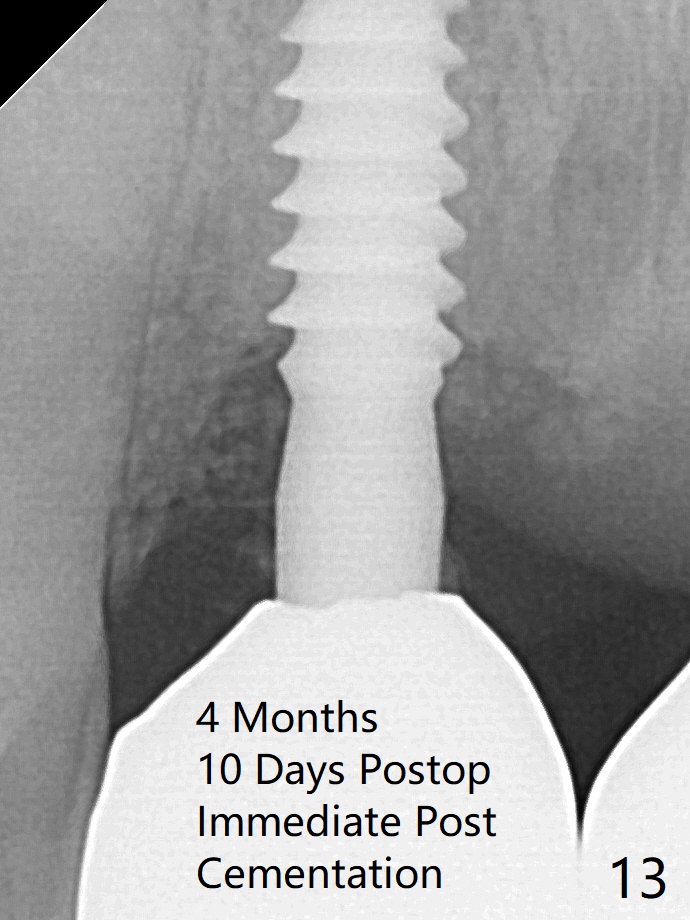

Allograft placed around the implant (Fig.9 *) appears to be able to prevent implant thread exposure 4 months postop (Fig.12). PA is taken when the crown is cemented (Fig13). Four months postop cementation of #8 crown (10 months postop), the patient returns because of #9 mobility (Fig.14).